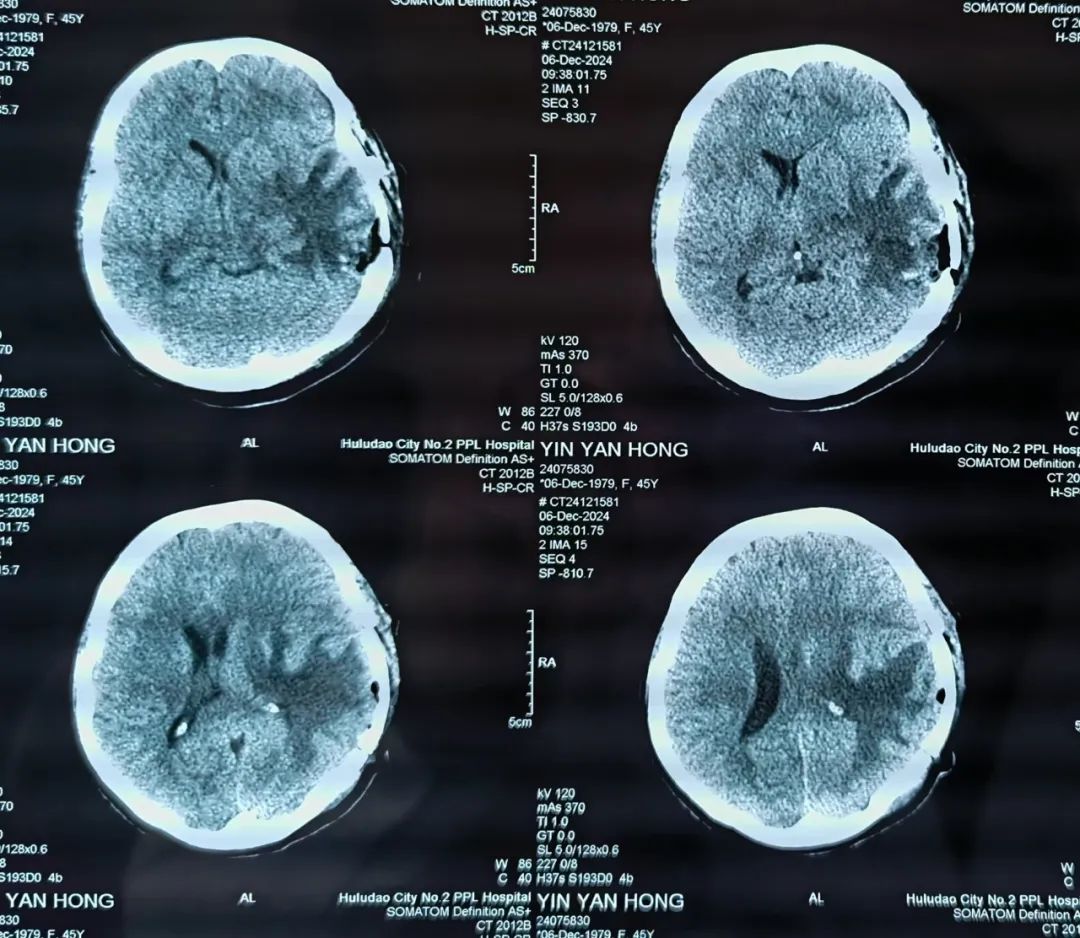

經(jīng)過(guò)桑主任顯微鏡下精雕細(xì)琢,完整切除腫瘤,手術(shù)非常順利。術(shù)后在神經(jīng)外科護(hù)理團(tuán)隊(duì)的精心護(hù)理下,患者病情恢復(fù)良好,頭痛、惡心、嘔吐癥狀消失,言語(yǔ)流利,四肢活動(dòng)良好,術(shù)后病理證實(shí)為腦轉(zhuǎn)移瘤。手術(shù)不但為患者減輕了痛苦,提高了生活質(zhì)量,也為后續(xù)的綜合治療贏得了時(shí)間。

患者術(shù)后CT影像